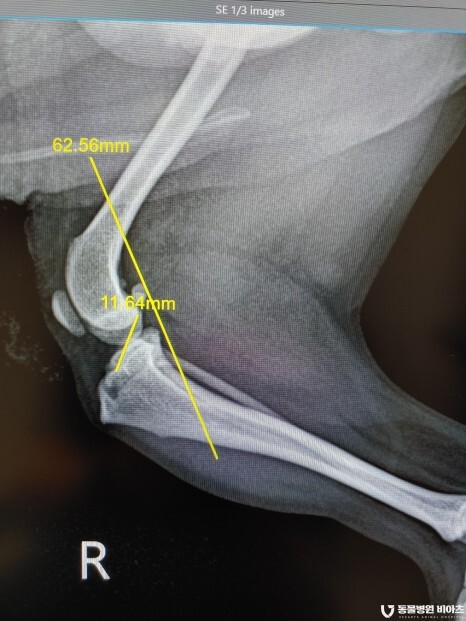

엑스레이 검사 결과

#전십자인대단열

#좌측 후지 슬개골 탈구 3기

#우측 후지 슬개골 탈구 2기

진단이 나왔습니다.